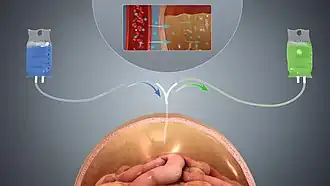

Dialysis

Dialysis is a treatment that substitutes for the function of normal kidneys. Dialysis may be instituted when approximately 85%–90% of kidney function is lost, as indicated by a glomerular filtration rate (GFR) of less than 15. Dialysis removes metabolic waste products as well as excess water and sodium (thereby contributing to regulating blood pressure); and maintains many chemical levels within the body. Life expectancy is 5–10 years for those on dialysis; some live up to 30 years. Dialysis can occur via the blood (through a catheter or arteriovenous fistula), or through the peritoneum (peritoneal dialysis). Hemodialysis is typically administered three times a week for several hours at free-standing dialysis centers, allowing recipients to lead an otherwise essentially normal life.[42]